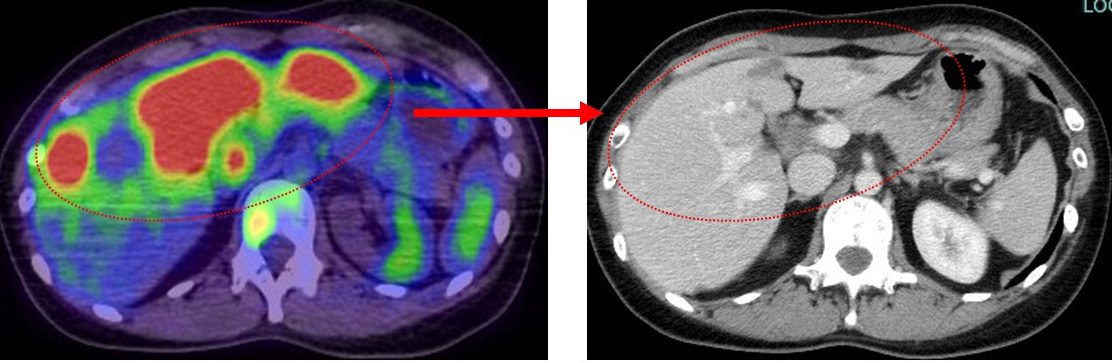

ここからが再発「メイン」である肝転移です。

かなり広範囲に多数ありました。

それが、EC終了後には…

凄いですよね?

正直、(ケモ前の)最初の状況(特に肝)から、ECだけでここまで改善するとは予想していなかったので(中間評価的なつもりで行ったのですが)私自身が度肝を抜かれるほどの効果です。